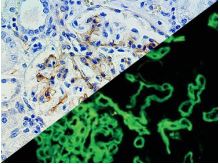

Bio SB has developed a highly sensitive Immunofluorescence and non-biotin monovalent Fab micropolymer IHC detection systems for the detection of IVD antibodies for Complement (C1q, C3c, C3d, C4c, C4d), Serum Proteins (Albumin and Fibrinogen) and Immunoglobulins (IgA, IgD, IgE, IgG, IgM, Kappa and Lambda) related to autoimmune conditions. Our innovative IF and IHC detection systems and high affinity antibodies, have opened the doors for a faster and accurate Immunofluorescence and Immunohistochemistry applicable to Autoimmune Disease like Nephropathies and Lupus.

These antibodies and detection systems are intended for use in Immunohistochemical (IHC) and Immunofluorescence (IF) applications of formalin-fixed paraffin-embedded tissues (FFPE), frozen tissue sections and cell preparations.